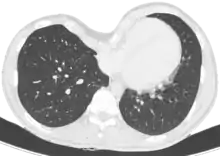

Le diagnostic est clinique, par l'examen de la déformation thoracique. On peut toutefois proposer la réalisation d'une tomodensitométrie thoracique, permettant le calcul de l'index de Haller, évaluant de manière objective la sévérité de la déformation et permettant de rechercher une compression cardiaque, trachéale ou œsophagienne. Des explorations fonctionnelles respiratoires évaluent l'impact de la déformation sur la fonction pulmonaire, et une épreuve d'effort recherche l'impact sur les capacités d'effort.